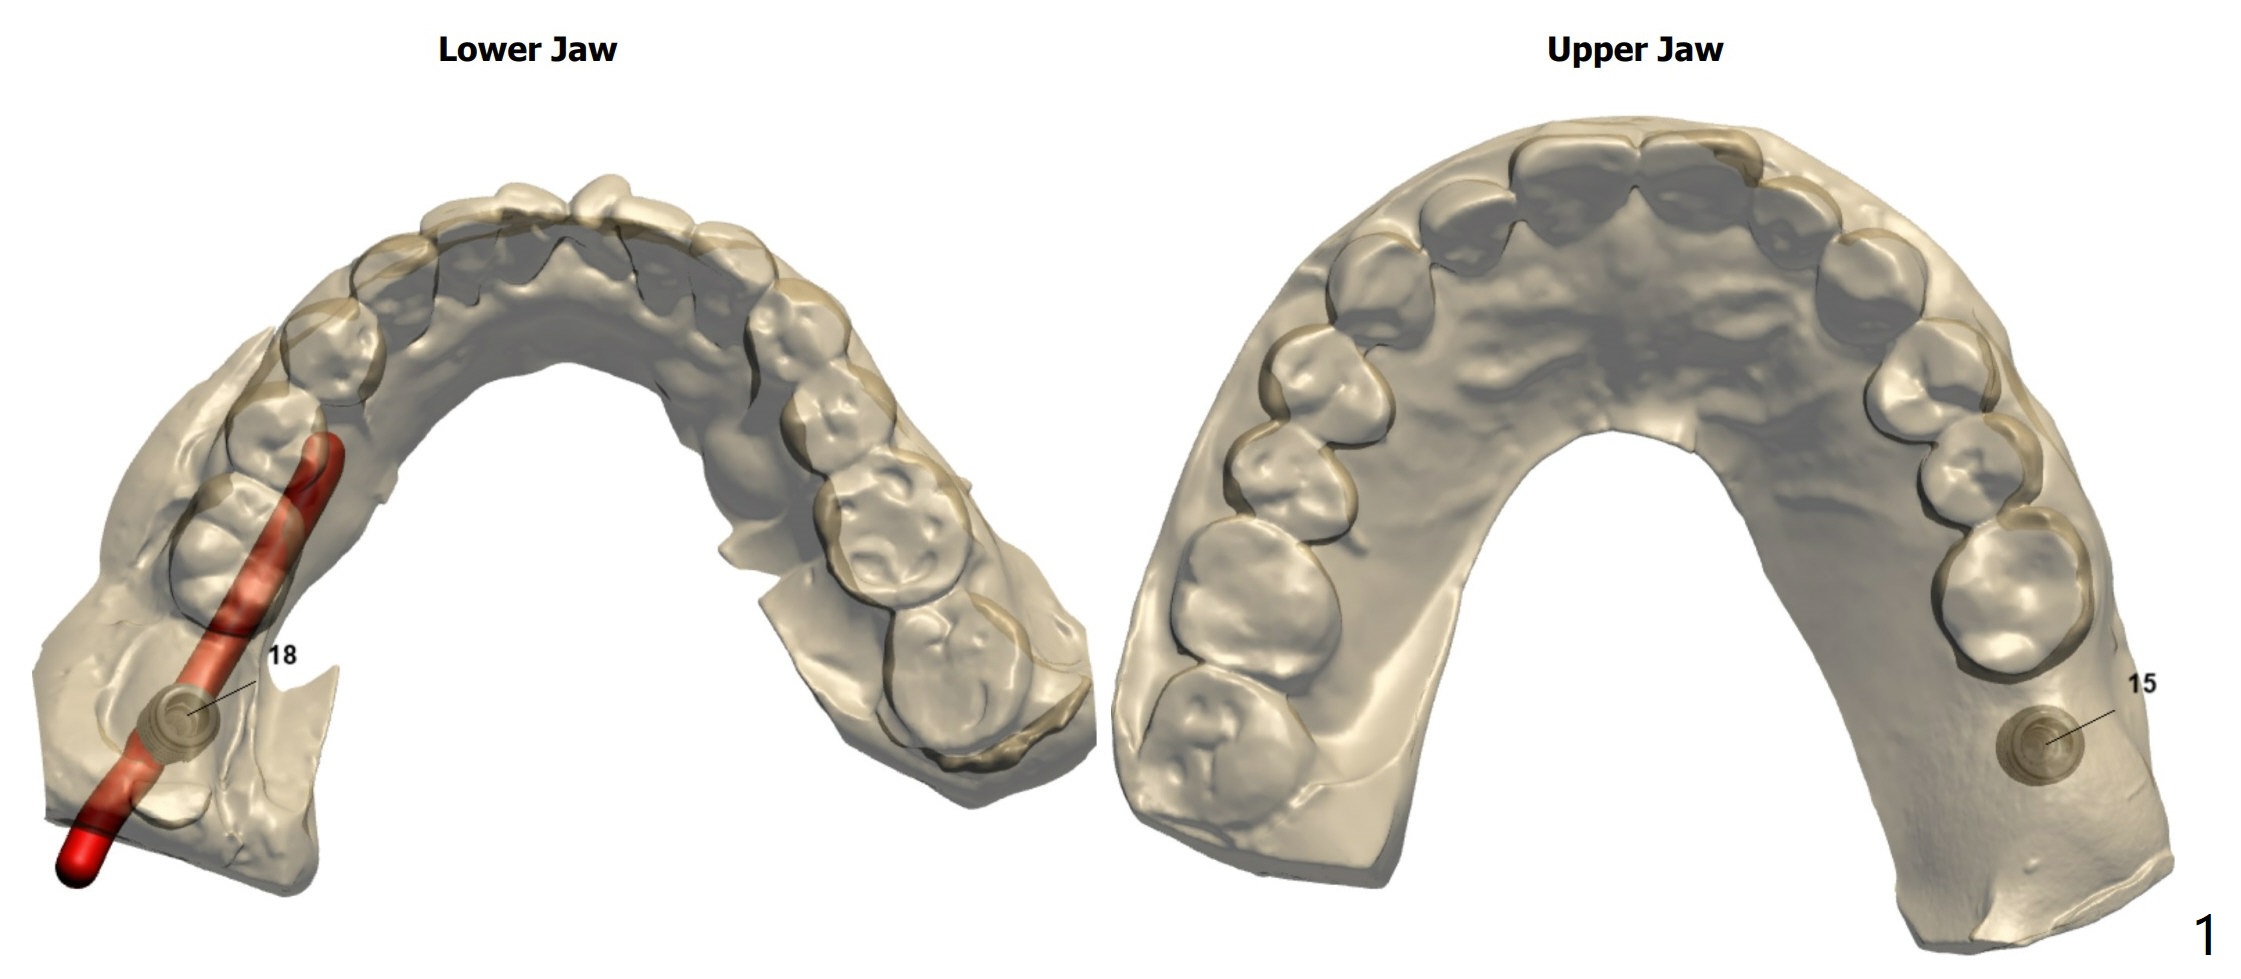

Short Implants

A 73-year-old woman

Xin Wei, DDS, PhD, MS 1st edition 03/15/2021, last revision 04/10/2021